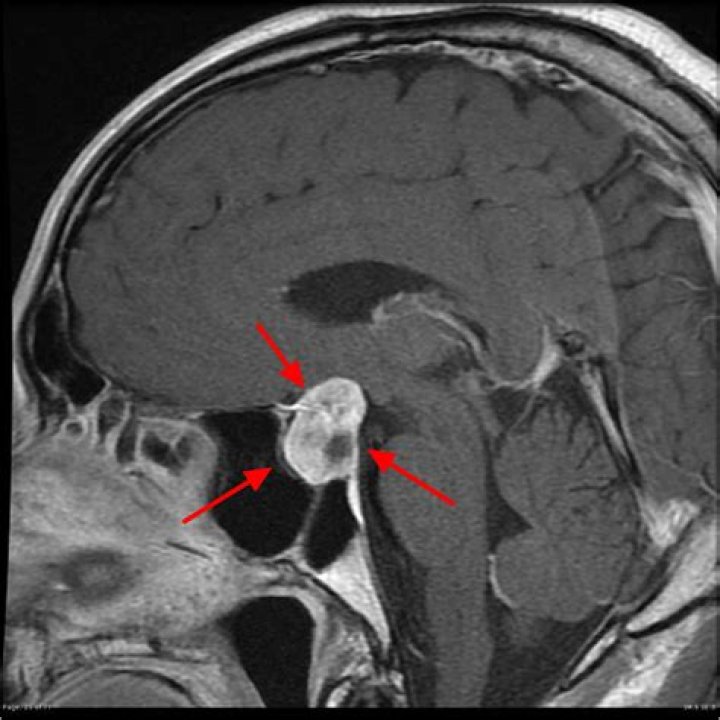

When pituitary tumors grow they can compress the above-mentioned structures and cause symptoms. Figure 1. A cross-section of the pituitary gland (green) shows its relationship to the optic chiasm, the sphenoid sinus, and the cavernous sinuses on each side.